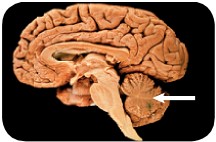

استخدم الشكل الآتي لتجيب عن السؤال 13.

13. إذا حدث ضرر للجزء المشار إليه في الصورة نتيجة حادث ما، فما أثر ذلك في الشخص؟

a. فقدان الذاكرة كليّاً أو جزئيّاً.

b. تغيّر في درجة حرارة الجسم.

c. عدم المحافظة على توازن الجسم.

d. تسارع في التنفس.